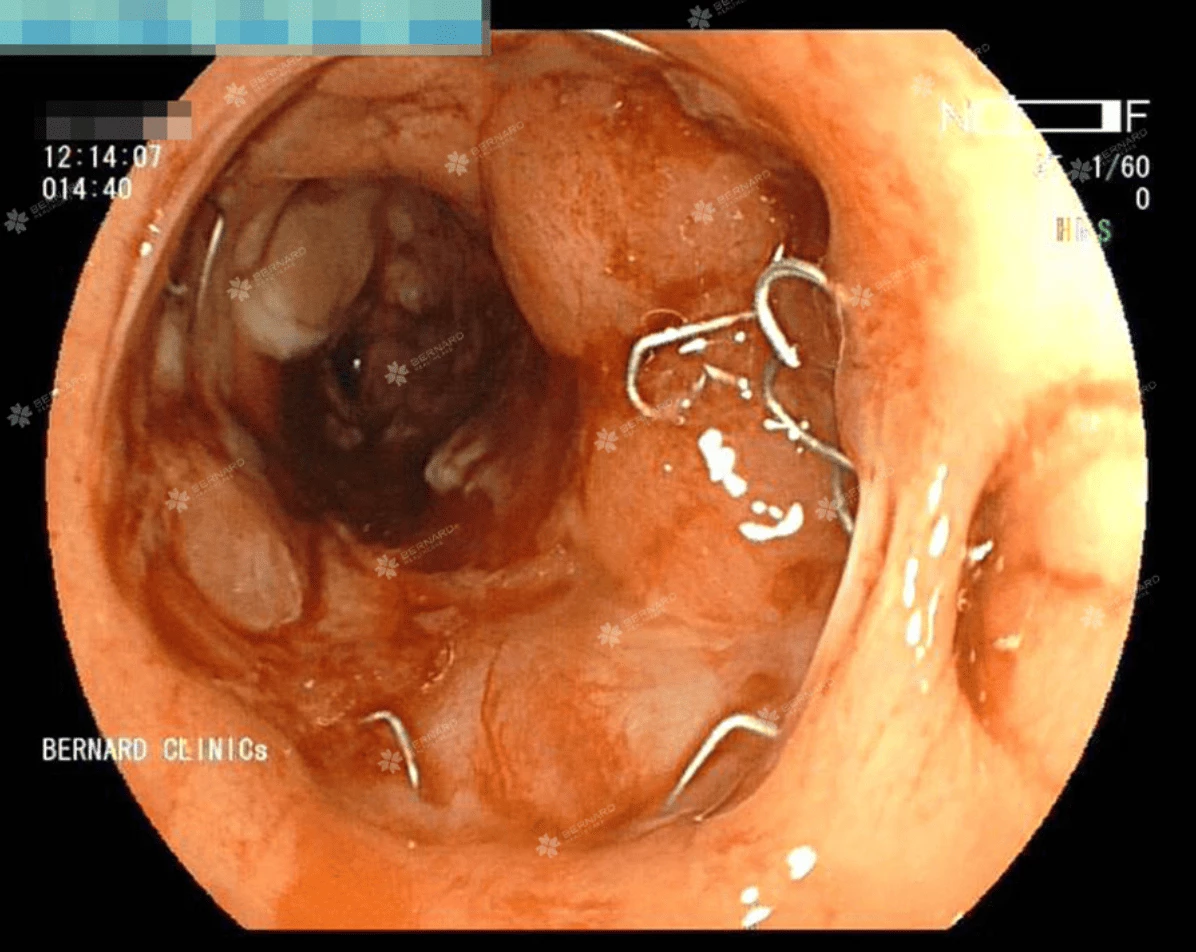

Nội soi toàn bộ đại trực tràng phát hiện ung thư tái phát và ung thư mới

Tại trực tràng, cách hậu môn khoảng 10cm, vị trí miệng nối sau phẫu thuật vẫn còn chỉ khâu xuất hiện khối u sùi, nhiễm cứng, làm hẹp lòng ruột, nghi ngờ tái phát ung thư trực tràng. Đáng lo ngại hơn khi soi về phía manh tràng, bác sĩ nội soi tìm thấy cách hậu môn nhân tạo #8cm có tổn thương u sùi, gây hẹp lòng.

Kết quả giải phẫu bệnh cho thấy, cả hai vị trí tổn thương tại miệng nối trực tràng và đại tràng trái đều là ung thư.